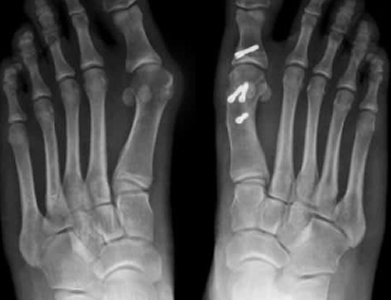

Osteotomy Surgery for Bunions

An osteotomy can be performed for other conditions, not just bunions. The term osteotomy refers to any surgery where bones are reshaped, but when talking about bunions, an osteotomy is performed to remove a bit of bone to help realign the toe and support the joint. Typically, pins and screws will be used to support the newly aligned bone and to keep the toe straight.

An exostectomy is the surgery to remove the bony bump that defines the bunion. This surgery is often just one part of the bunion surgery and is paired with soft tissue procedures and a technique to straighten the toe and support joint health. Removing the bunion lump alone will not solve the problem. As you can see from x-rays, bunions include significant shifts in how the toe bone lies. To fully solve a bunion, other steps must be taken to straighten the toe.

Post-surgery appointments: Your medical team will schedule a series of appointments for you after your surgery to make sure you’re progressing as expected and to prevent complications. These appointments are very important and will include x-rays, dressing changes, exercises to begin working on range of motion, pain medications if necessary, and could include splinting or a toe spacer.